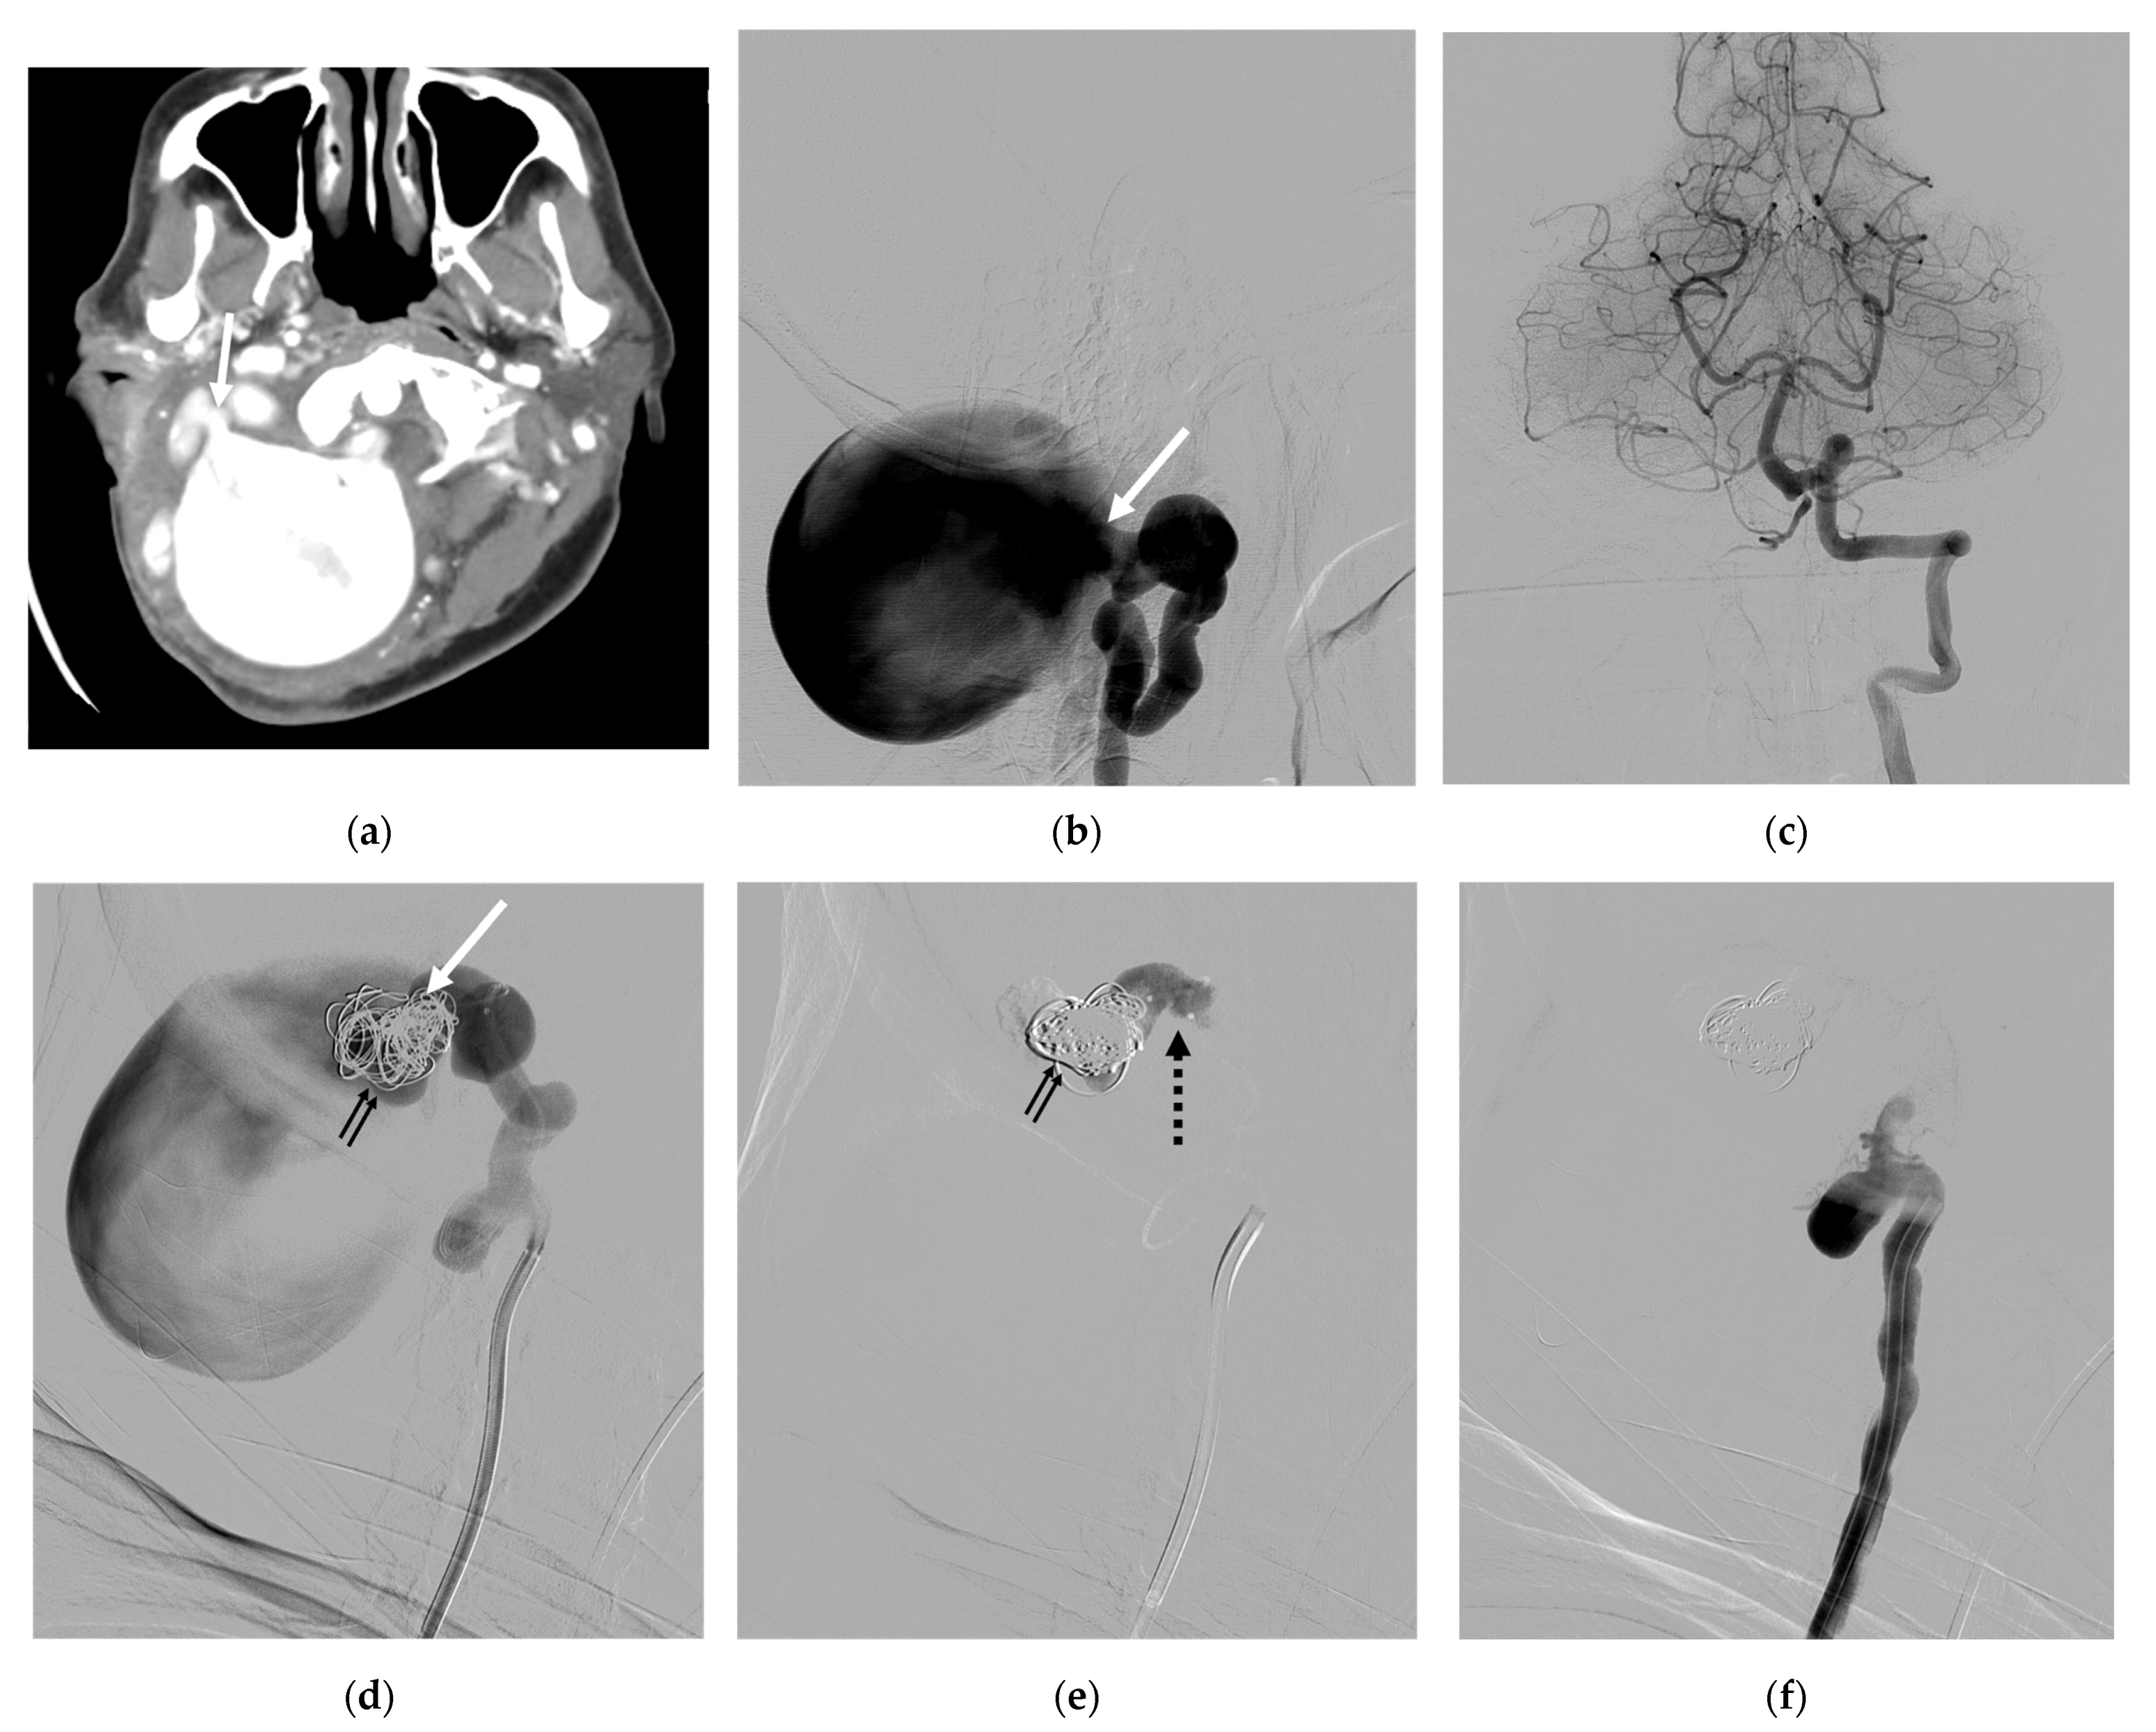

| 8 | F | 33 | Neck mass; tinnitus; paresthesia of left arm; ataxia | NF-1 | S | IJV; VVP with venous pouch | Y | B, C, and NBCA | O | Improved | Vertigo |

| 9 | F | 25 | Neck mass | NF-1 | S | VVP with venous pouch | Y | C and NBCA | O | Improved | None |

| 10 | F | 27 | Incidental finding | NF-1 | S | Lateral epidural vein with venous pouch | Y | NBCA | O | Improved | None |